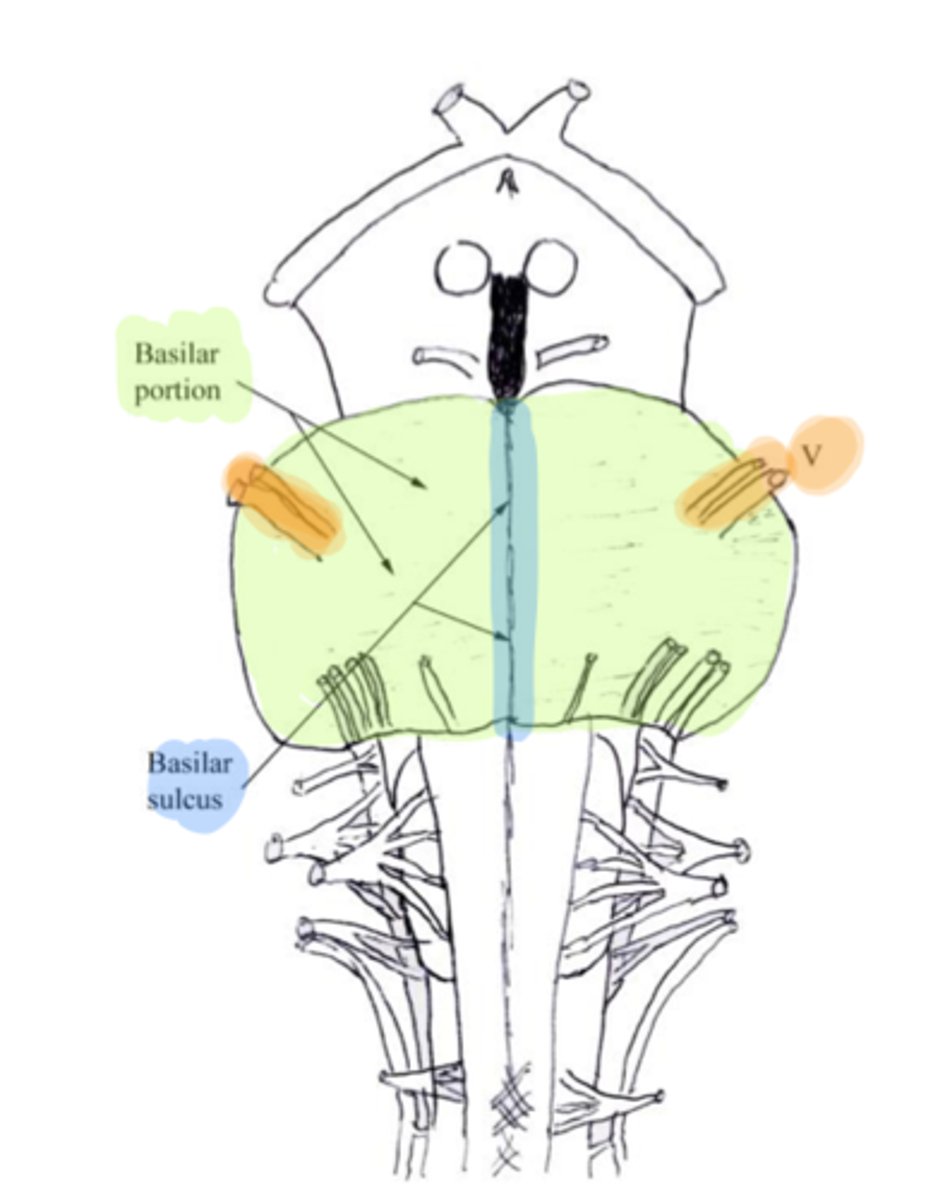

refers to the large round protuberance on the ventral pons that represents a "bridge" of horizontally oriented fibers connecting the right and left sides

basilar portion

longitudinal midline groove of the pons that is the superior continuation of the ventral median sulcus/fissure, containing a namesake artery

basilar sulcus

white matter stalks that connect the pons to the cerebellum

middle cerebellar peduncles

What is the only cranial nerve that attaches to the pons?

CN V

A

basilar portion

B

basilar sulcus

C

CN V

B

middle cerebellar peduncles

tegmentum